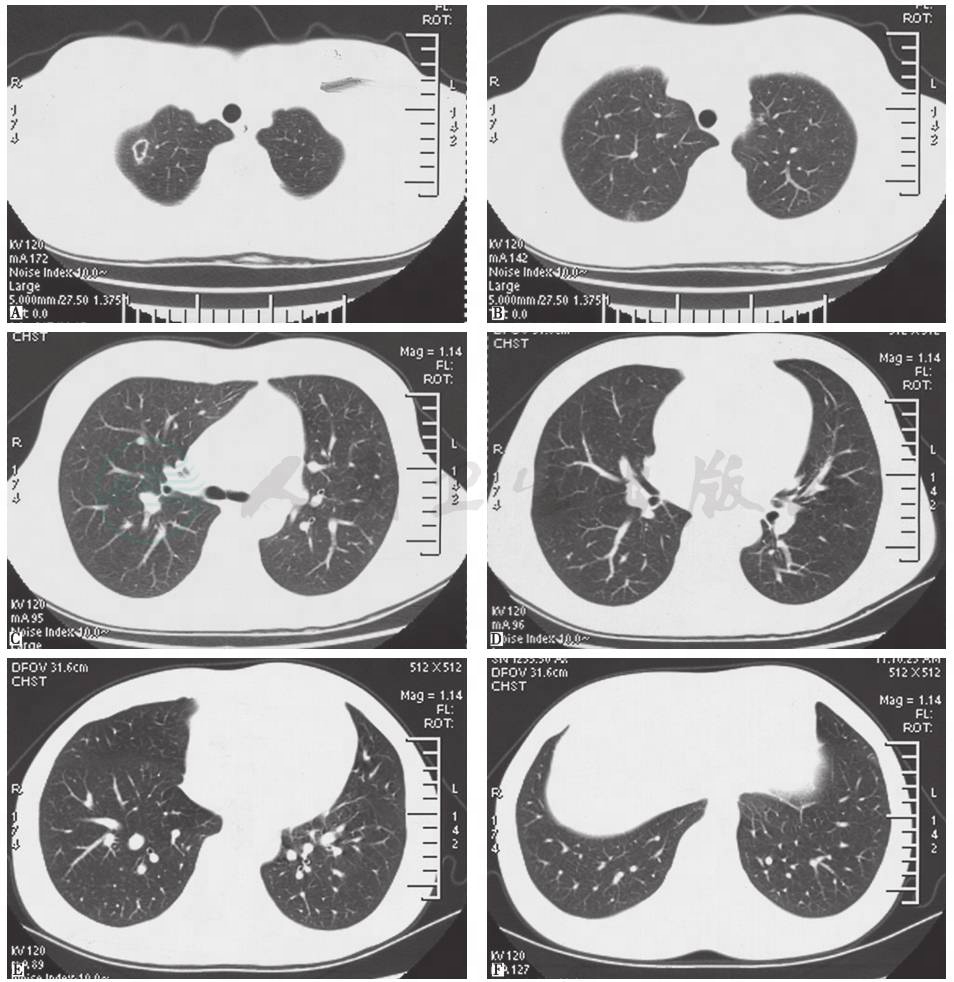

血管炎、系统性红斑狼疮、白塞病等疾病进展累及肺部时,患者可出现发热、咯血等症状,肺内可出现多灶、多形态病灶。其中,白塞病是一种可累及全身的血管炎性疾病,最常见的表现为反复口腔溃疡、生殖器溃疡和虹膜炎,肺部表现包括肺动脉瘤、肺动脉栓塞、肺部结节(图6)、磨玻璃影、胸膜肥厚、胸腔积液、淋巴结增大、肺气肿或肺大疱。本例患者有白塞病家族史,故应警惕该病。

图6 白塞病胸部影像学表现

男性患者,32岁,主因发热、咳嗽、咯血、体重下降2个月入院;反复出现口腔溃疡、生殖器溃疡、下肢结节性红斑,皮肤针刺试验阳性;肺部实变活检提示出血、机化性血栓、血管增生。胸部X线片可见双肺多发斑片影伴左侧胸腔积液(A);胸部CT提示双肺多发结节、实变,左侧胸腔积液(B)。诊断为白塞病